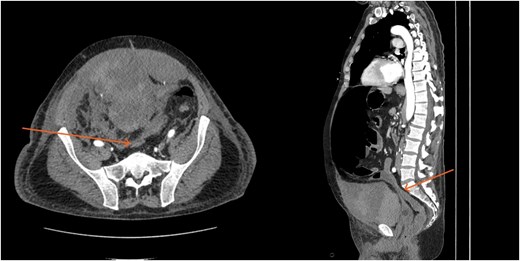

A massive transfusion protocol was initiated, and the patient received four units of packed red blood cells, six units of fresh frozen plasma, two units of platelets, and bicarbonate boluses. A CT abdomen and pelvis was performed to reassess the RSH, revealing an interval enlargement (15.3 × 10.7 × 20.4 cm) with a focal blush at the inferior portion, concerning for active extravasation (Fig. 3). The patient was hemodynamically stabilized and underwent inferior vena cava (IVC) filter placement once his hemoglobin reached 8 g/dl.

A follow-up CT scan performed 2 days after placement of IVC filter and stopping anticoagulation showed further enlargement of the hematoma (17.5 × 14 × 25.7 cm) and ongoing bleeding. Interventional radiology performed bilateral inferior epigastric artery angiograms, which revealed no ongoing artery bleeding but truncation of the right inferior epigastric artery. Empiric Gelfoam embolization was performed on the left inferior epigastric artery (Fig. 4).